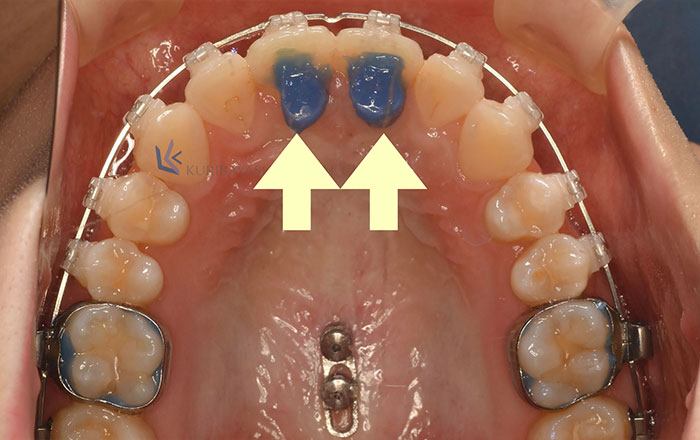

2.バイトプレート

バイトプレートは、上の前歯の裏につけます。

上顎前突(出っ歯)の場合など、上下の前歯に隙間があり、歯が当たっていない時にバイトプレートを装着することで、前歯がしっかり当たるようにします。

バイトプレートがない場合は、上下の前歯が当たっていないため、上下の奥歯に過度な力が加わり、奥歯へ負担がかかったままです。

また、奥歯に負担がかかったままだと、加えられている力により、矯正治療で歯が動かしにくくなります。

バイトプレートをつけることで、上記の改善が見込めます。